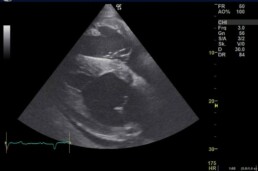

- Ultraschall des Herzens: deutlicher Herzbeutelerguss, Bewegungsstörungen des rechten Herzens

Nach 6 Monaten zeigte sich im Ultraschall weiterhin ein deutlicher Herzbeutelerguss. Die Prognose bei einer Perikarditis ist meist vorsichtig bis ungünstig, da die Erkrankung chronisch verlaufen oder sich verschlimmern kann.